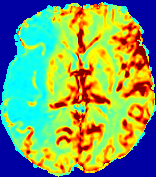

4.3.2 Diffusion Imaging via Advection-Diffusion

Slice #1Slice #2Slice #3Slice #4Slice #5Slice #6Dgtsuperscript𝐷gtD^{\text{gt}}Refer to captionRefer to captionRefer to captionRefer to captionRefer to captionRefer to captionDestsuperscript𝐷estD^{\text{est}}Refer to captionRefer to captionRefer to captionRefer to captionRefer to captionRefer to captionRefer to caption0.300.300.300.240.240.240.180.180.180.120.120.120.060.060.060.000.000.00(mm2/s)𝑚superscript𝑚2𝑠(mm^{2}/s)𝐕est𝟐subscriptnormsuperscript𝐕est2\|\bf{V}^{\text{est}}\|_{2}Refer to captionRefer to captionRefer to captionRefer to captionRefer to captionRefer to captionRefer to caption0.00300.00300.00300.00240.00240.00240.00180.00180.00180.00120.00120.00120.00060.00060.00060.00000.00000.0000(mm/s)𝑚𝑚𝑠(mm/s)

Figure 15: PIANO identifiability testing: diffusion imaging via advection-diffusion. Top row shows Dgtsuperscript𝐷gtD^{\text{gt}} used for simulating ground truth pure diffusion. Rows below show the estimated Destsuperscript𝐷estD^{\text{est}} and 𝐕est2subscriptnormsuperscript𝐕est2\|{\bf{V}}^{\text{est}}\|_{2} on corresponding slices. Note that the plotted value scale for 𝐕est2subscriptnormsuperscript𝐕est2\|{\bf{V}}^{\text{est}}\|_{2} is 0.01 of that for Dgtsuperscript𝐷gtD^{\text{gt}} and Destsuperscript𝐷estD^{\text{est}}.

Similarly, we test the behavior of PIANO when estimating both advection and diffusion from a pure diffusion-driven process. The goal is to determine if PIANO is able to recognize that there is only diffusion governing the given concentration time-series. We use the same ‘Diffusion Imaging’ data simulation of Sec. 4.2.1 as the concentration dataset, PIANO estimates both velocity 𝐕estsuperscript𝐕est{\bf{V}}^{\text{est}} and diffusivity Destsuperscript𝐷estD^{\text{est}}. Estimation results in Fig. 15 confirm PIANO’s identifiability again: the estimated 𝐕est2subscriptnormsuperscript𝐕est2\|{\bf{V}}^{\text{est}}\|_{2} is almost invisible compared to Destsuperscript𝐷estD^{\text{est}}, even plotted with a 1%percent11\% value range compared to that for Destsuperscript𝐷estD^{\text{est}}. On the other hand, Destsuperscript𝐷estD^{\text{est}} achieves comparable estimation performance as ‘Diffusion Imaging via Diffusion’ in which PIANO predicts Destsuperscript𝐷estD^{\text{est}} alone (shown in Fig. 13).